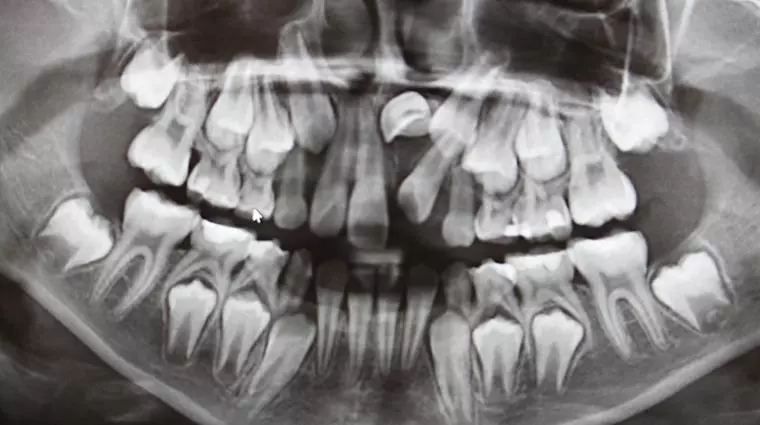

口腔全景片是一种全景式的X射线照片,能够显示口腔内的所有牙齿、上颌骨和下颌骨的情况。该检查非常适用于检测智齿、根管治疗、口腔肿瘤等病症。相比其他X射线照片,口腔全景片的拍摄时间很短,只需数秒钟即可完成,同时它还能够提供更广阔的观察范围,非常适合初步检查和快速诊断。

全景片